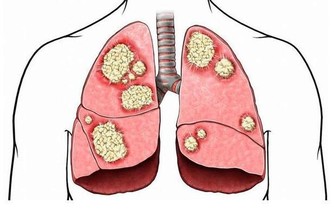

*****1.健康問題*****

過度勞累會對您的身心健康產生深遠的負面影響。無論是背痛,沮喪,心臟問題,肥胖症,還是經常生病,都要考慮工作是否是原因。您會知道過度勞累何時會影響您的健康,並且您將不得不決定是否值得這樣做。